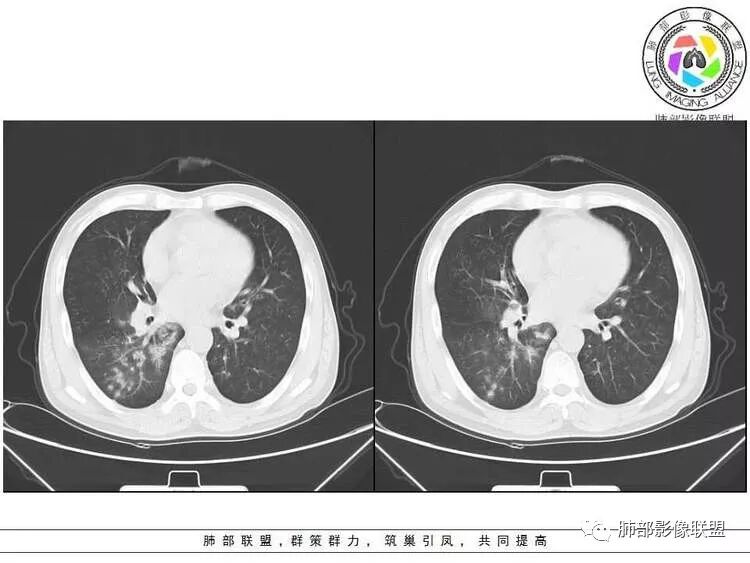

远端确实有膨隆,边缘凹凸不平,换个角度,这个病灶紧贴着斜裂外带。

南边:紧贴着斜裂过来的一个病灶,它的特点是:外围大,内带小。它整个下叶背段体积与对侧相比稍微缩小一点,但是缩小地不是很厉害。外支朝前下走了,仔细看血管,肺动脉走行自然,直达远端。远端实变区是肉芽肿成分,稍微有一点低密度,没有明显坏死,稍微有一点点坏死。而且附近有很多卫星灶,附近很多斑片影,有一些明显有气道壁增厚,细支气管炎的特点,还有就是下叶其他段很多斑片状影。换个角度,第一如果是肺癌,刚才看到PET-CT提示肺癌伴阻塞性肺炎,这个是不符合的。第二如果是肺癌阻塞性肺炎,近端血管肺动脉走行不会那么自然集聚的,这个是不符合的。理由是:如果这个病灶是肺癌,那么明显属于中央型肺癌,中央型肺癌的特点是近端大,远端小,近端是一个肿块,远端阻塞,远端阻塞是阻塞性炎症或者不张,它应该体积缩小,斑片状实变,不会这么密实。刚才有老师提到支气管,这个片有缺陷的地方,给的图像好像那层,如果把其他图像拿开再重叠一下。

右肺下叶背断肿块,外围大,内带相对狭长         远端有膨隆,边缘模糊、凹凸不平         血管走形自然,病灶近端支气管通畅,沿支气管树蔓延         周边有多发病灶,多为磨玻璃密度且边界不清。

轻度强化         PET-CT:SUV 7.5,高摄取